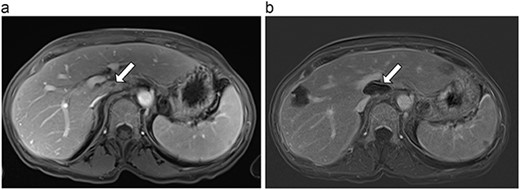

(a) Pre-ablation MRI demonstrating 14 mm lesion in caudate lobe of liver. (b) Post-ablation MRI (23 days postoperatively) demonstrating 23.8 mm complete ablation of caudate lesion.

| 4 (6a,b) | 51, M | Colon adenocarcinoma | 6 cycles FOLFOX | 4 | Laparoscopic microwave ablation | 14 | 23.8 | 9.8 | 13 | Yes |